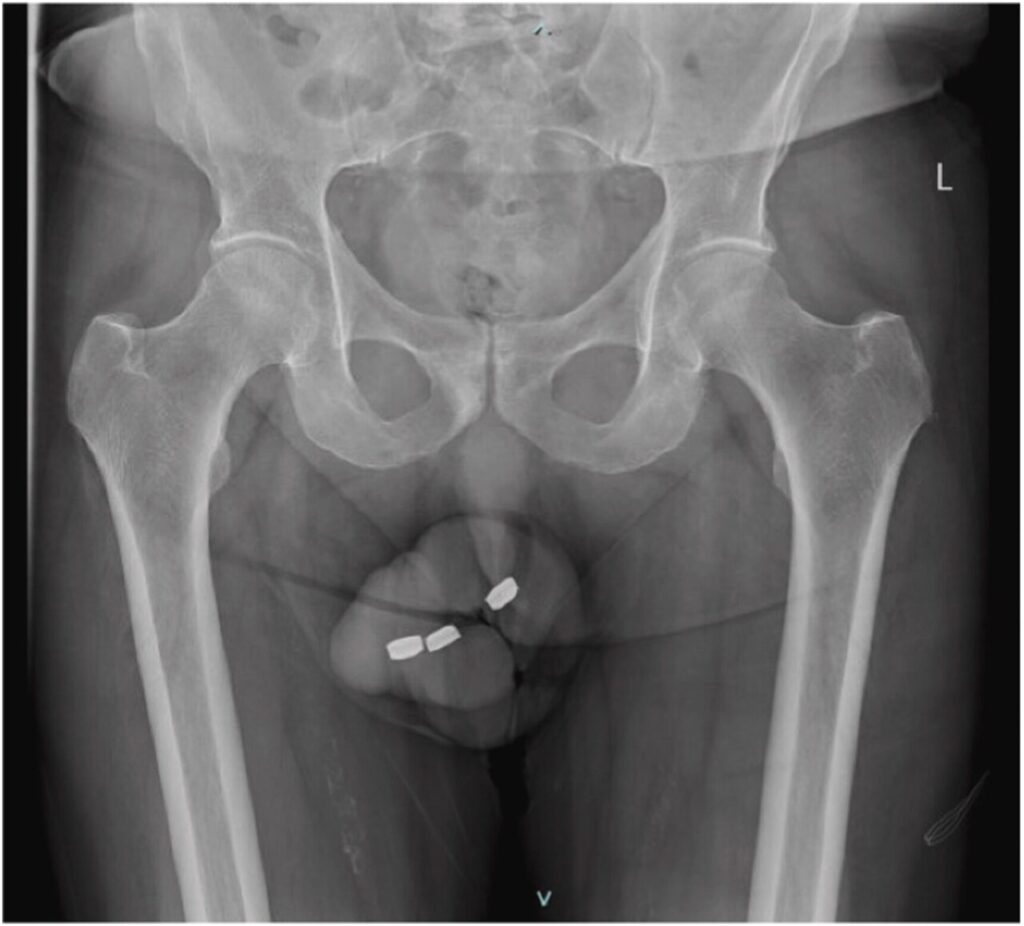

image-45-32

Foto: Reprodução/ Urology Case Reports

Ao chegar ao hospital, o paciente não conseguia urinar e estava com o órgão todo inchado. Além disso, a bateria enfiada por último havia se danificado lá dentro e os médicos temiam o vazamento de elementos corrosivos no corpo do paciente. Os médicos que atenderam o paciente relataram ter tentado retirar as baterias com pinças, mas a dor impediu que o procedimento atingisse seu objetivo. O recurso seguinte foi sedar o idoso e retirar as baterias em uma operação cirúrgica.

Durante a cirurgia, os médicos descobriram que a uretra do paciente estava queimada por conta do vazamento das substâncias corrosivas. Eles cuidaram das queimaduras, prescreveram antibióticos e deram alta para o homem após três dias. Dez dias depois, o homem retornou ao hospital com novo inchaço no pênis e muita secreção de pus acumulada no órgão, além de dificuldade de retração do prepúcio.

Os médicos drenaram todo o líquido do pênis em uma nova cirurgia e descobriram que 8 cm da uretra havia necrosado, o que obrigou-os a retirar parte do órgão do paciente, com a substituição do canal por um catéter. O tecido ao redor foi raspado para evitar novas infecções.